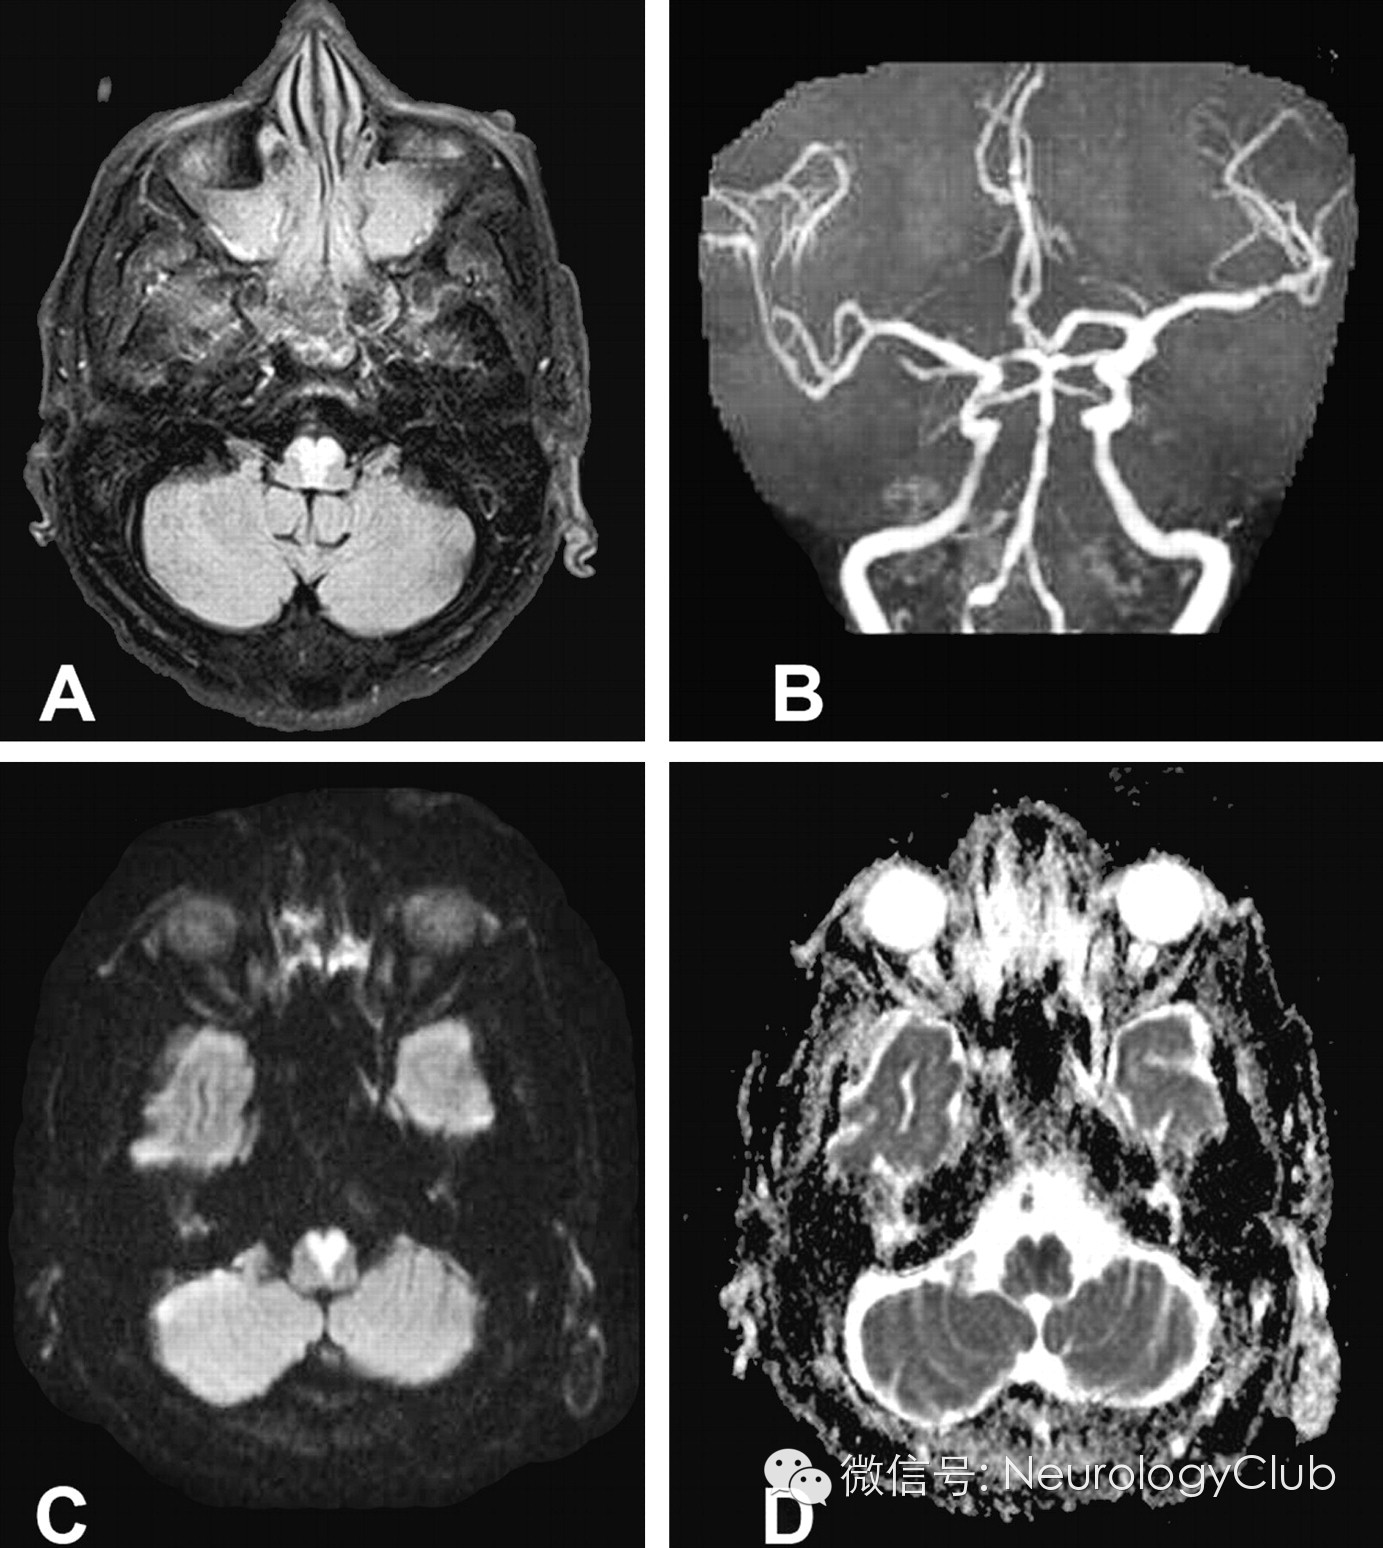

延髓内侧由椎动脉和脊髓前动脉分支供血,其中延髓内侧上1/3由椎动脉旁分支供应,下2/3由双侧脊髓前动脉及其汇合而成的前正中动脉延髓支供应。双侧延髓内侧梗死血管病理学改变以大动脉粥样硬化最为常见,其次是小穿支动脉病变,另外也有栓塞、动脉夹层、动脉炎或合并先天血管变异等病因报道。影像学特点头颅MRI检查,尤其是DWI对双侧延髓内侧梗死的早期诊断有很大的帮助。其影像学表现为磁共振显示双侧延髓内侧类似“心型”或“Y形”的长T1长T2信号影,DWI高信号,ADC低信号,符合梗死改变,具有特征性的诊断意义。

引自:Bilateral medial medullary infarction presenting as Guillain-Barré-like syndrome.Clin Neurol Neurosurg.2011Sep;113(7):589-91.